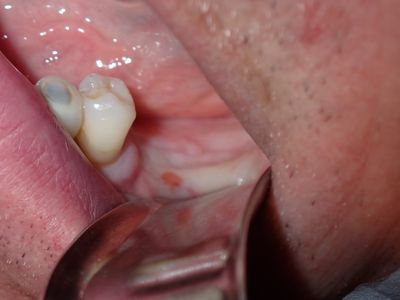

large amount of bone loss at time of exo 36/37 done 2 months ago. Good healing of bone except for small socket area at 36 region. buccal bone lower than palatal about 1mm, decided to place tissue level implants opposed to grafting, gaining back height is unlikely, difficult access case with large tongue. Implants placed with 36 about 1.5mm buccal exposed, 37, .5mm mesial exposed, healing abutments palced grafted all sites with sticky bone followed by collagen membrane soaked in prf fluid, 2 holes cut for implants. additonal fibrin membrance placed on buccal prior to suturing.